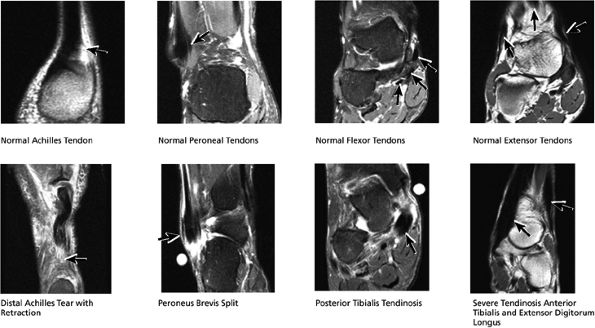

The lateral tendons (the peroneus longus and brevis tendons)

The medial tendons (the posterior tibialis, the flexor digitorum longus, and the flexor hallucis longus tendons)

The anterior tendons (the tibialis anterior, the extensor hallucis longus, and the extensor digitorum longus tendons)

The posterior tendons (the Achilles and plantaris tendons)

FIGURE 5.27 ● Axial anatomy of the ankle and foot. (A) The flexor digitorum longus, flexor hallucis longus, peroneus brevis, soleus, and extensor digitorum muscles are examined at this level for strain, tears, or fatty atrophy that may suggest denervation. (B) The tibialis anterior, extensor hallucis longus, and extensor digitorum longus tendons are examined on every ankle MR examination. Extensor tendon pathology is frequently overlooked if these tendons are not included as part of the ankle checklist. (C) Tears and sprains of the anterior syndesmotic ligament are a frequent cause of persistent ankle pain following ankle sprain. The syndesmotic ligaments are thick, tough ligaments that are important ankle stabilizers, and delayed diagnosis of syndesmotic tears may result in significant degenerative arthrosis at the tibiotalar joint due to the resulting ankle instability. The syndesmotic ligaments course obliquely inferiorly from the tibia to the fibula and are not usually visualized in their entirety on a single axial image; rather, their course is followed on at least two or three successive axial images. (D) The peripheral margin of the peroneal tendons and tibialis posterior tendon should normally never extend beyond the peripheral margins of the lateral and medial malleoli, respectively. Tendon subluxation around the posterior corner of either malleolus is indicative of a tear of the overlying flexor retinaculum (medially) or peroneal retinaculum (laterally). When the retinacula are torn, the tendon is free to intermittently sublux or dislocate, leading to tendon degeneration, pain, and tendon dysfunction. (E) Suspected osteochondral lesions of the talar dome are visualized and further characterized on axial images through the top of the talar dome. (F) The peroneus brevis tendon may normally appear somewhat flattened. However, as the tendon degenerates, it becomes U-shaped and drapes around the anterior aspect of the peroneus longus and becomes impinged between the peroneus longus tendon and the lateral malleolus. With further degeneration, the peroneus brevis may split or completely rupture. (G) Evidence of anterior talofibular ligament injury is visualized on the majority of MR ankle examinations and appears as thickening, intermediate signal with ill-defined fibers, or attenuation of the ligament. This is commonly asymptomatic. (H) Because the flexor hallucis longus tendon sheath communicates with the tibiotalar joint, fluid may normally be present within the tendon sheath in proportion to the amount of fluid in the tibiotalar joint. If there is fluid within the tendon sheath out of proportion to that seen in the tibiotalar joint, tenosynovitis is most likely present. The finding of flexor hallucis longus tenosynovitis should prompt a search for an os trigonum, as impingement of the flexor hallucis longus tendon between an os trigonum and the posterior tibial plafond is a common cause for FHL tenosynovitis. (I) The calcaneofibular ligament (CFL) passes anterior and medial to the peroneal tendons. On the image at which the CFL passes directly medial to the peroneus brevis tendon, the appearance of the peroneus brevis and the CFL side by side is occasionally mistaken for a split peroneus brevis tendon. (J) Dilated posterior tibial veins within the tarsal tunnel occasionally compresses the tibial nerve. In the setting of clinical suspicion for tarsal tunnel syndrome or if there is evidence of muscle denervation on MR images, the size of the posterior tibial veins should be described. (K) The spring ligament is identified at this axial image location, extending from the anteromedial calcaneus to the posteromedial navicular. Tears of the spring ligament may result in medial instability and hindfoot valgus. (L) The posterior tibialis tendon (PTT) may normally become thickened and fan-like as it passes posterior to its navicular insertion (prior to also inserting on the cuneiforms and the base of the second through fourth metatarsals). In the absence of other findings, the thickening of the PTT at this level should not be mistaken for focal tendinosis. (M) On inferior images through the ankle, Lisfranc's ligament is occasionally included in the FOV. Lisfranc's ligament extends from the medial cuneiform to the base of the second metatarsal. If Lisfranc's ligament is included in the FOV, the status of the ligament should be described, as undiagnosed Lisfranc ligament tears can lead to debilitating midfoot arthrosis. (N) As the medial and lateral tendons turn from their vertical course to a horizontal course along the plantar aspect of the foot, the tendons may demonstrate a magic-angle artifact, causing the tendons to appear gray on short-TE images, mimicking tendinosis. Correlation with images using longer TE values is advised in such situations.